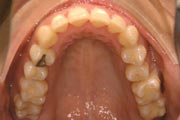

Crowding

Before